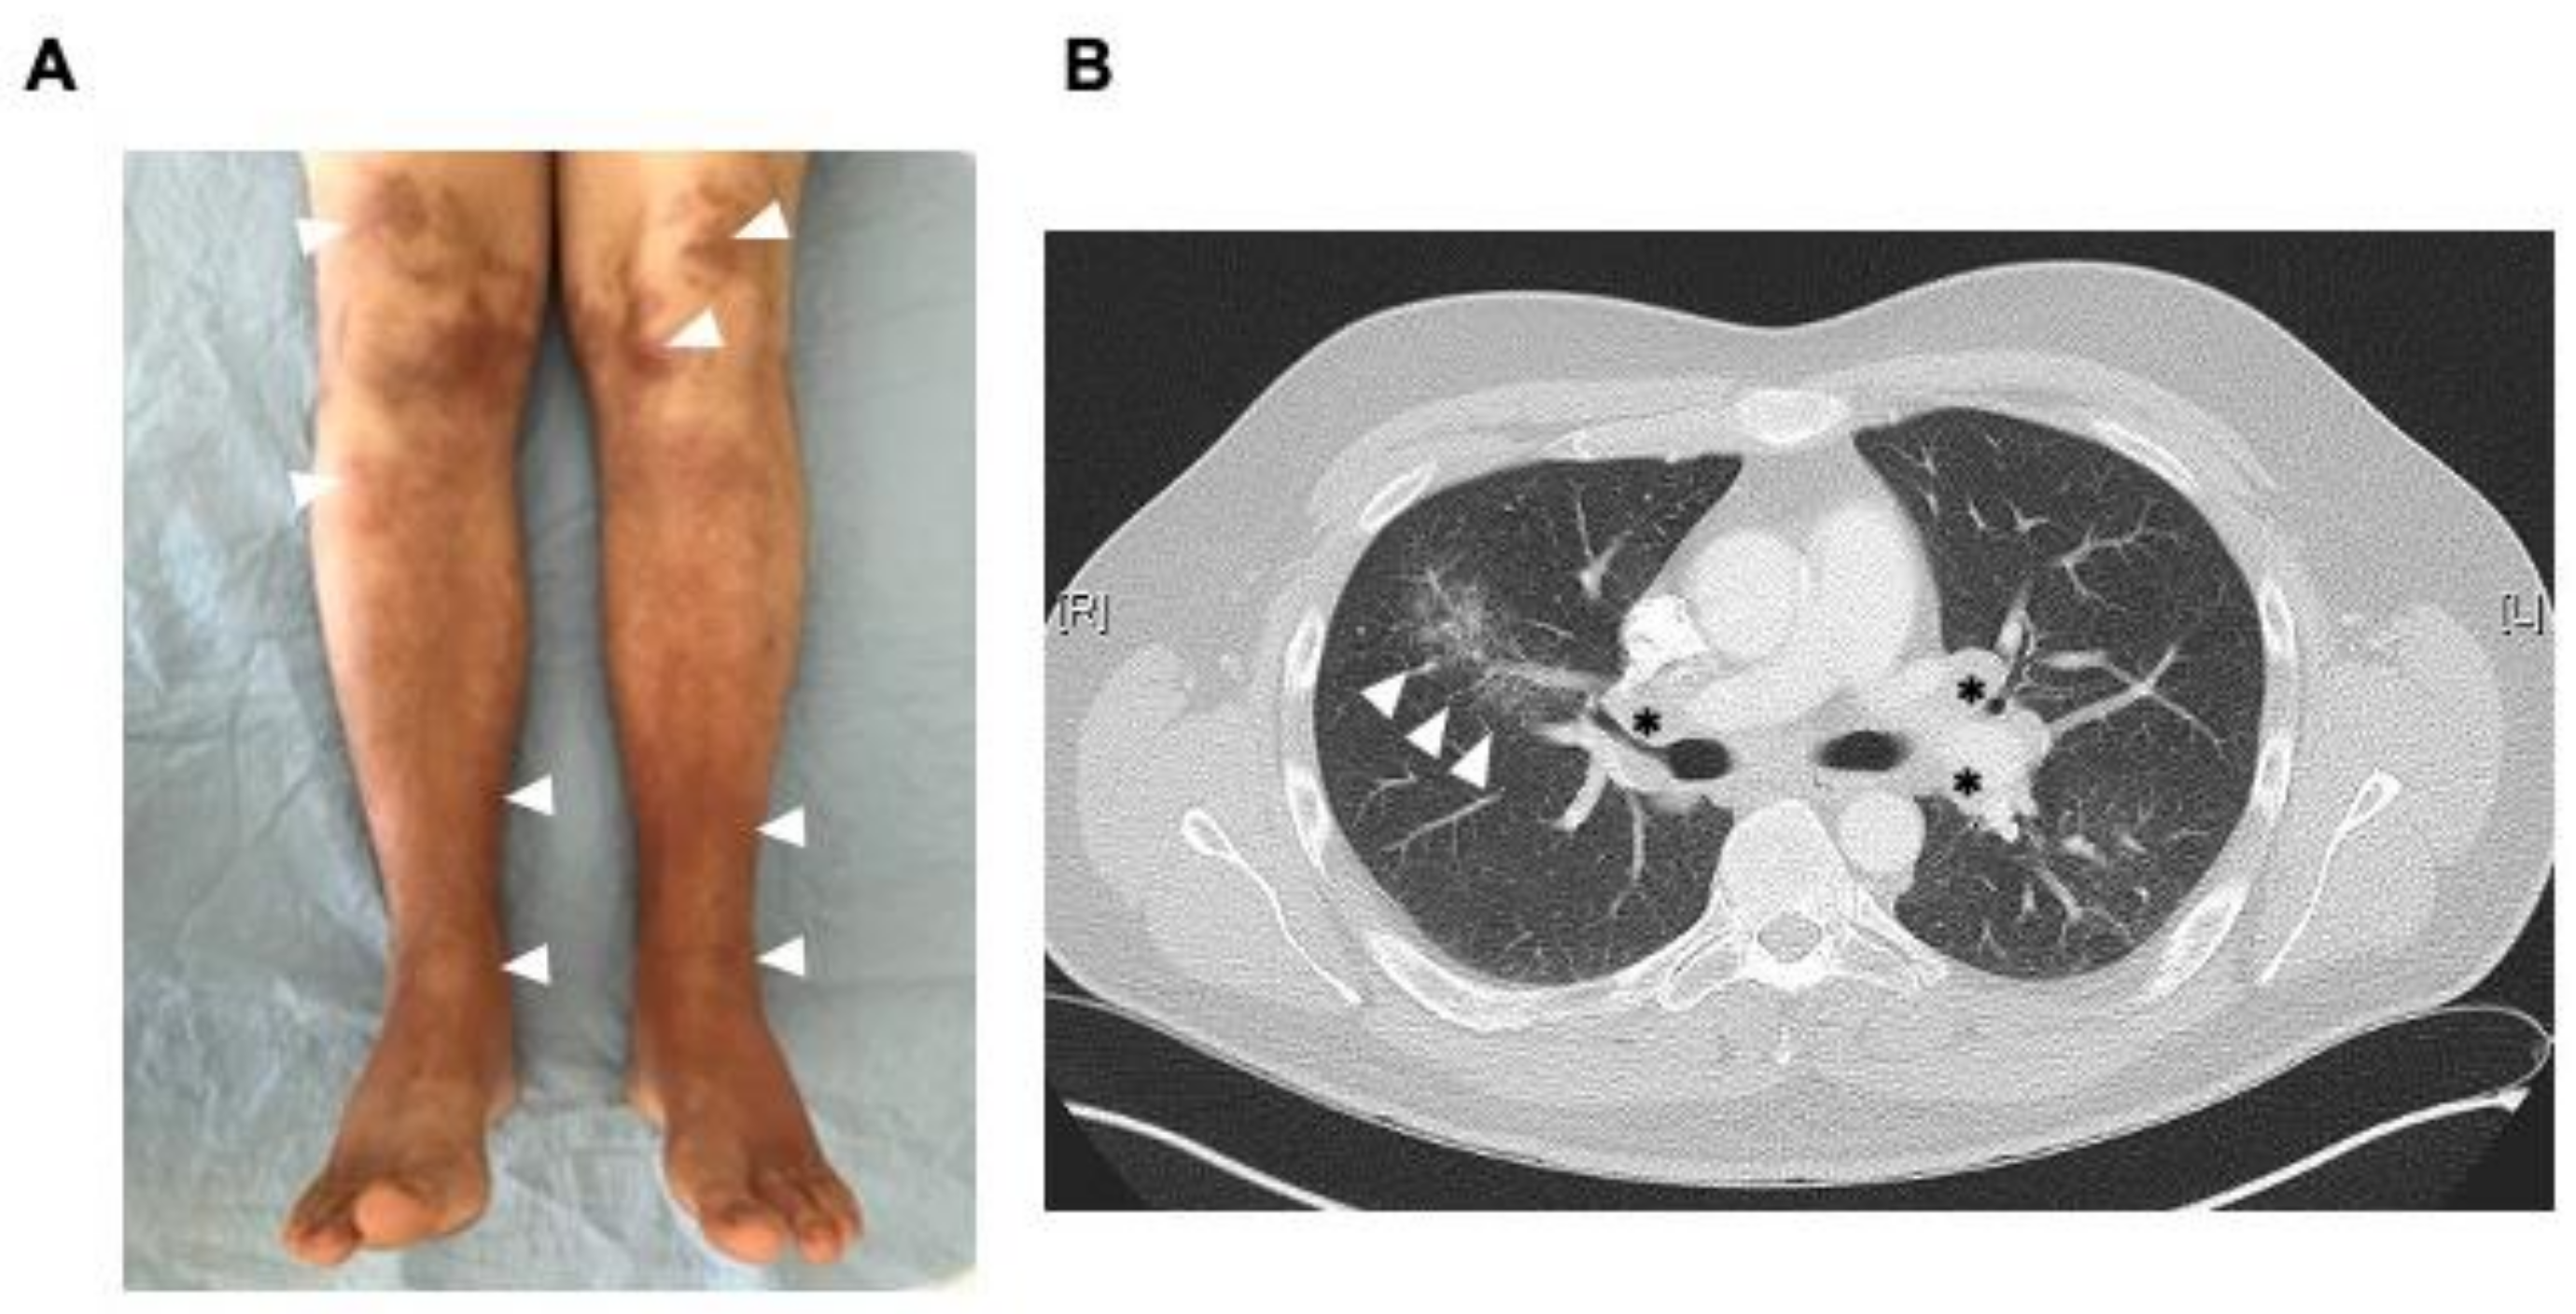

2. Case Reports